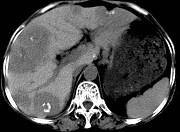

问题 女,55岁,腹胀,肛门闭气,消瘦乏力,肝区疼痛,CT检查如图,最可能的诊断为 ( )

选项 A.多发性肝脓肿 B.肝癌肝内转移 C.肝淋巴管瘤 D.肝脏囊腺瘤 E.结肠癌肝转移

答案 E